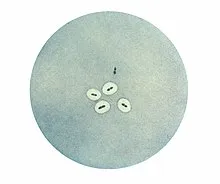

Welche 2 wichtigen <i>Labortests </i>gibt es für die Identifikation von <b>Pneumokokken</b>?<br><br>① {{c1::Quellung Reaktion}}<br>② {{c1::Optochin Sensitivität}}

① Antiserum (Serum+Antikörper gg. Kapsel) + Pneumokokken = Aufquellung

① Antiserum (Serum+Antikörper gg. Kapsel) + Pneumokokken = Aufquellung<br>② Unterscheidung S. viridans+pneumoniae <br> ↳ Optochin auf Platte → <i>S. pneumoniae</i> Wachstum wird inhibiert; <i>S. viridans</i> wächst weiter

<img alt="Quellung reaction - Wikipedia" src="8bf063fefcc26ae3ff8d374d3cc82838.webp"><br>Quellung